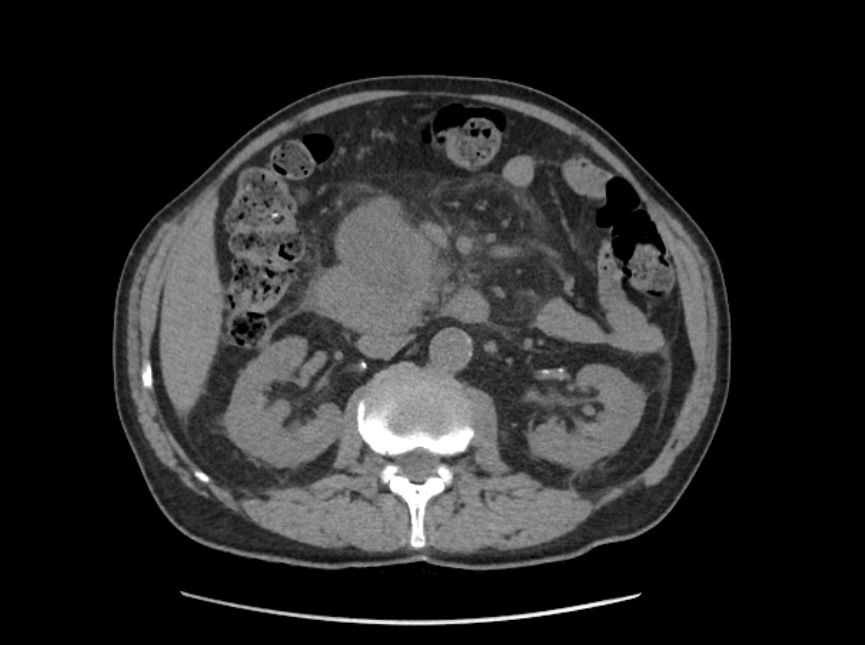

La litiasis y la dilatación de la vesícula biliar encontrada en la ecografía clínica no justificaba todo el cuadro, por lo que solicitamos ecografía reglada al equipo de radiología. En ella informan marcada dilatación de la vía biliar intrahepática, con un colédoco de hasta 15 mm, y estructura mamelonada de aproximadamente 7 cm en cabeza pancreática. Se completa estudio con Tomografía Axial Computarizada que confirma masa en cabeza pancreática compatible con adenocarcinoma que condiciona dilatación de la vía biliar retrógrada.